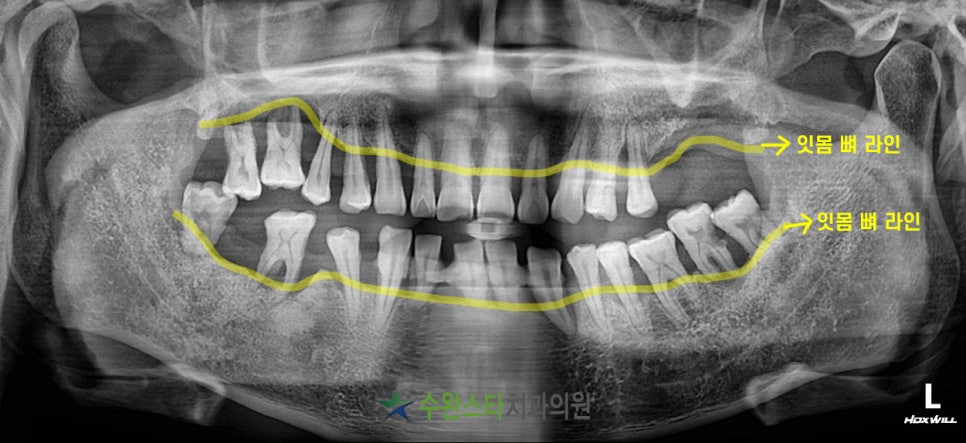

수술 전 엑스레이, 40대 남성(2022.10)

노랗게 표시한 부분이 잇몸 라인인데요.

한눈에 봐도 상,하악 잇몸 뼈 라인이

무너져 내려 치아 뿌리를

완전히 감싸주지 못하고 있는 모습입니다.

잇몸이 내려가는 주요한 이유는

치주 질환입니다.